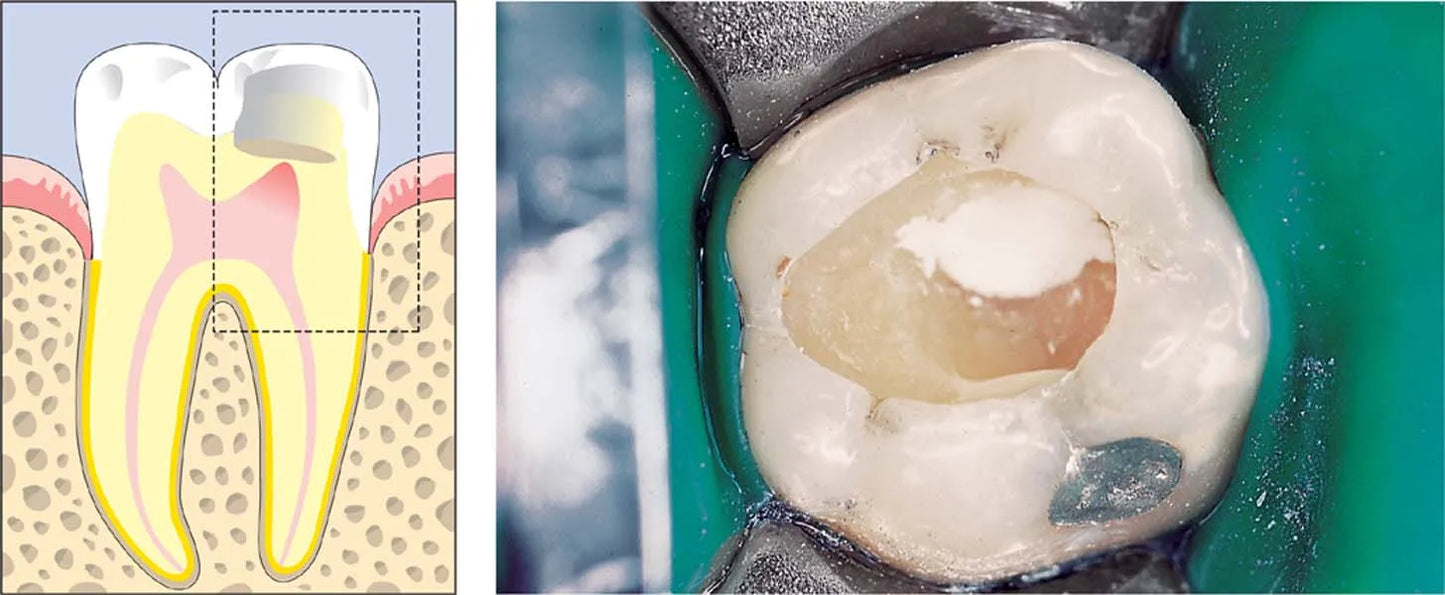

ReGlass - Lc is a light curing resin modified Bioactive Glass filler flowable composite for cavity linings, pit and fissure sealing and smaller surface lesions under ATR.

As Cavity Liner

- ReGlass – Lc is inserted with applying needle cannula (recommended single use) directly into caries free prepared cavity area in 1-2 mm thickness

- Etching and bonding is advised depending upon type of your cavity and approximate distance with pulp tissue.

- Do not use ReGlass – Lc on margin of cavity and enamel surface